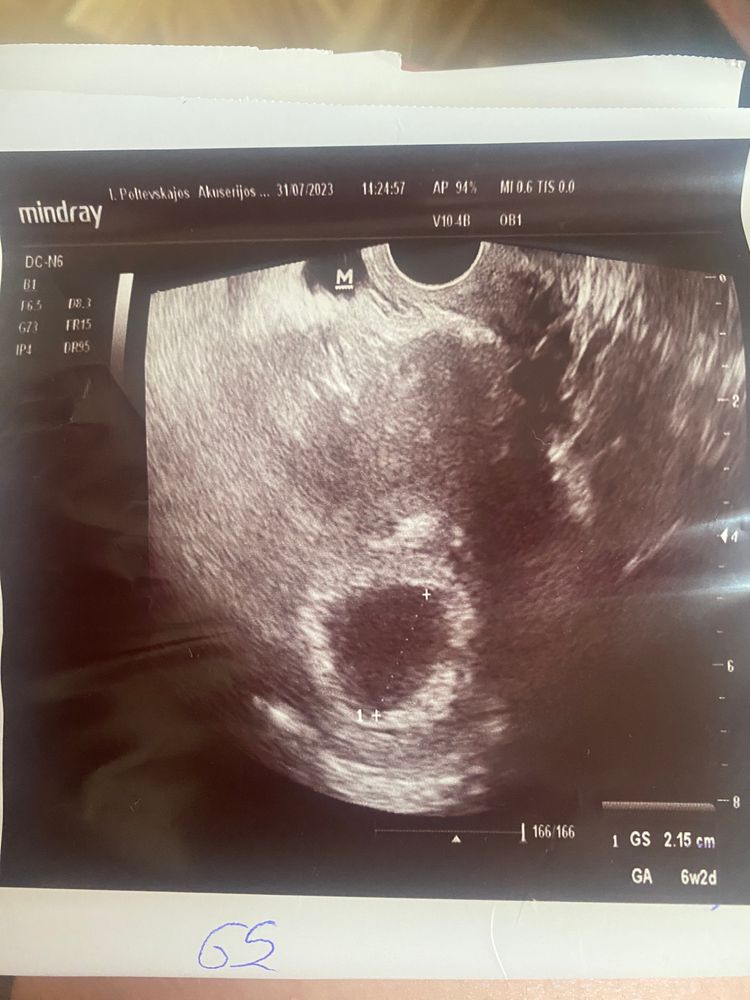

Напомню свою историю, может кому пригодится)4 дня назад поставили срок 6,2 недели, что никак не сходится ни с первым узд ни с размером плодного яйца(2,15 -4 &nb

Размер 2.15

По узи прставили срок 6.2 недели.. яйцо плодное 2.15 см!.. а в середине пусто.. сказала еще недельку подождать и что то делать..